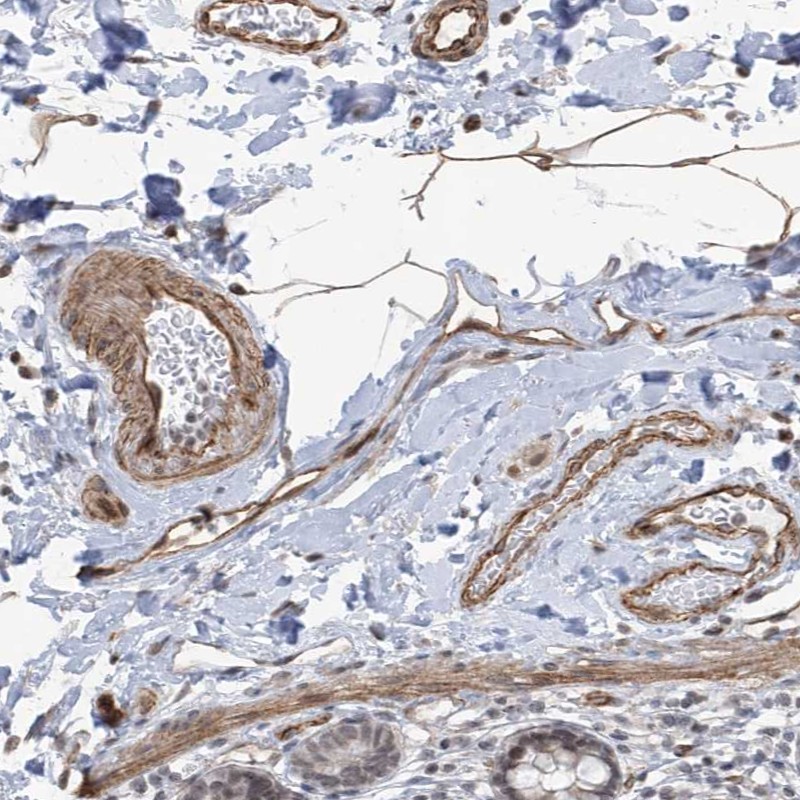

Immunohistochemical staining of human smooth muscle shows cytoplasmic positivity in smooth muscle cells.